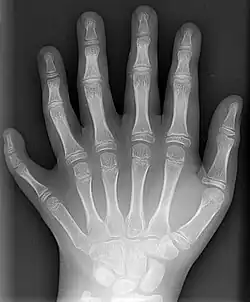

Polidaktylia (polydaktylia) (gr. polýs – wiele, mnogi; dáktylos – palec) – wada wrodzona polegająca na obecności dodatkowego palca bądź palców, najczęściej I lub V.

Dodatkowe palce mogą być cechą zaburzeń chromosomowych (np. zespół Pataua), zaburzeń monogenowych autosomalnie dominujących lub o etiologii nieznanej. Polidaktylia może być wadą izolowaną lub stanowić część obrazu klinicznego wielu zespołów wad wrodzonych. Jest to najczęściej występująca wada kończyn górnych. Niekiedy występuje łącznie z palcozrostem (syndaktylia)[1].